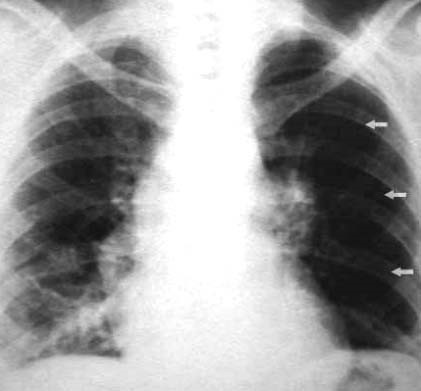

Qual alteração radiológica é possível ser vista neste RX de tórax?

É sinal sugestivo de quê?